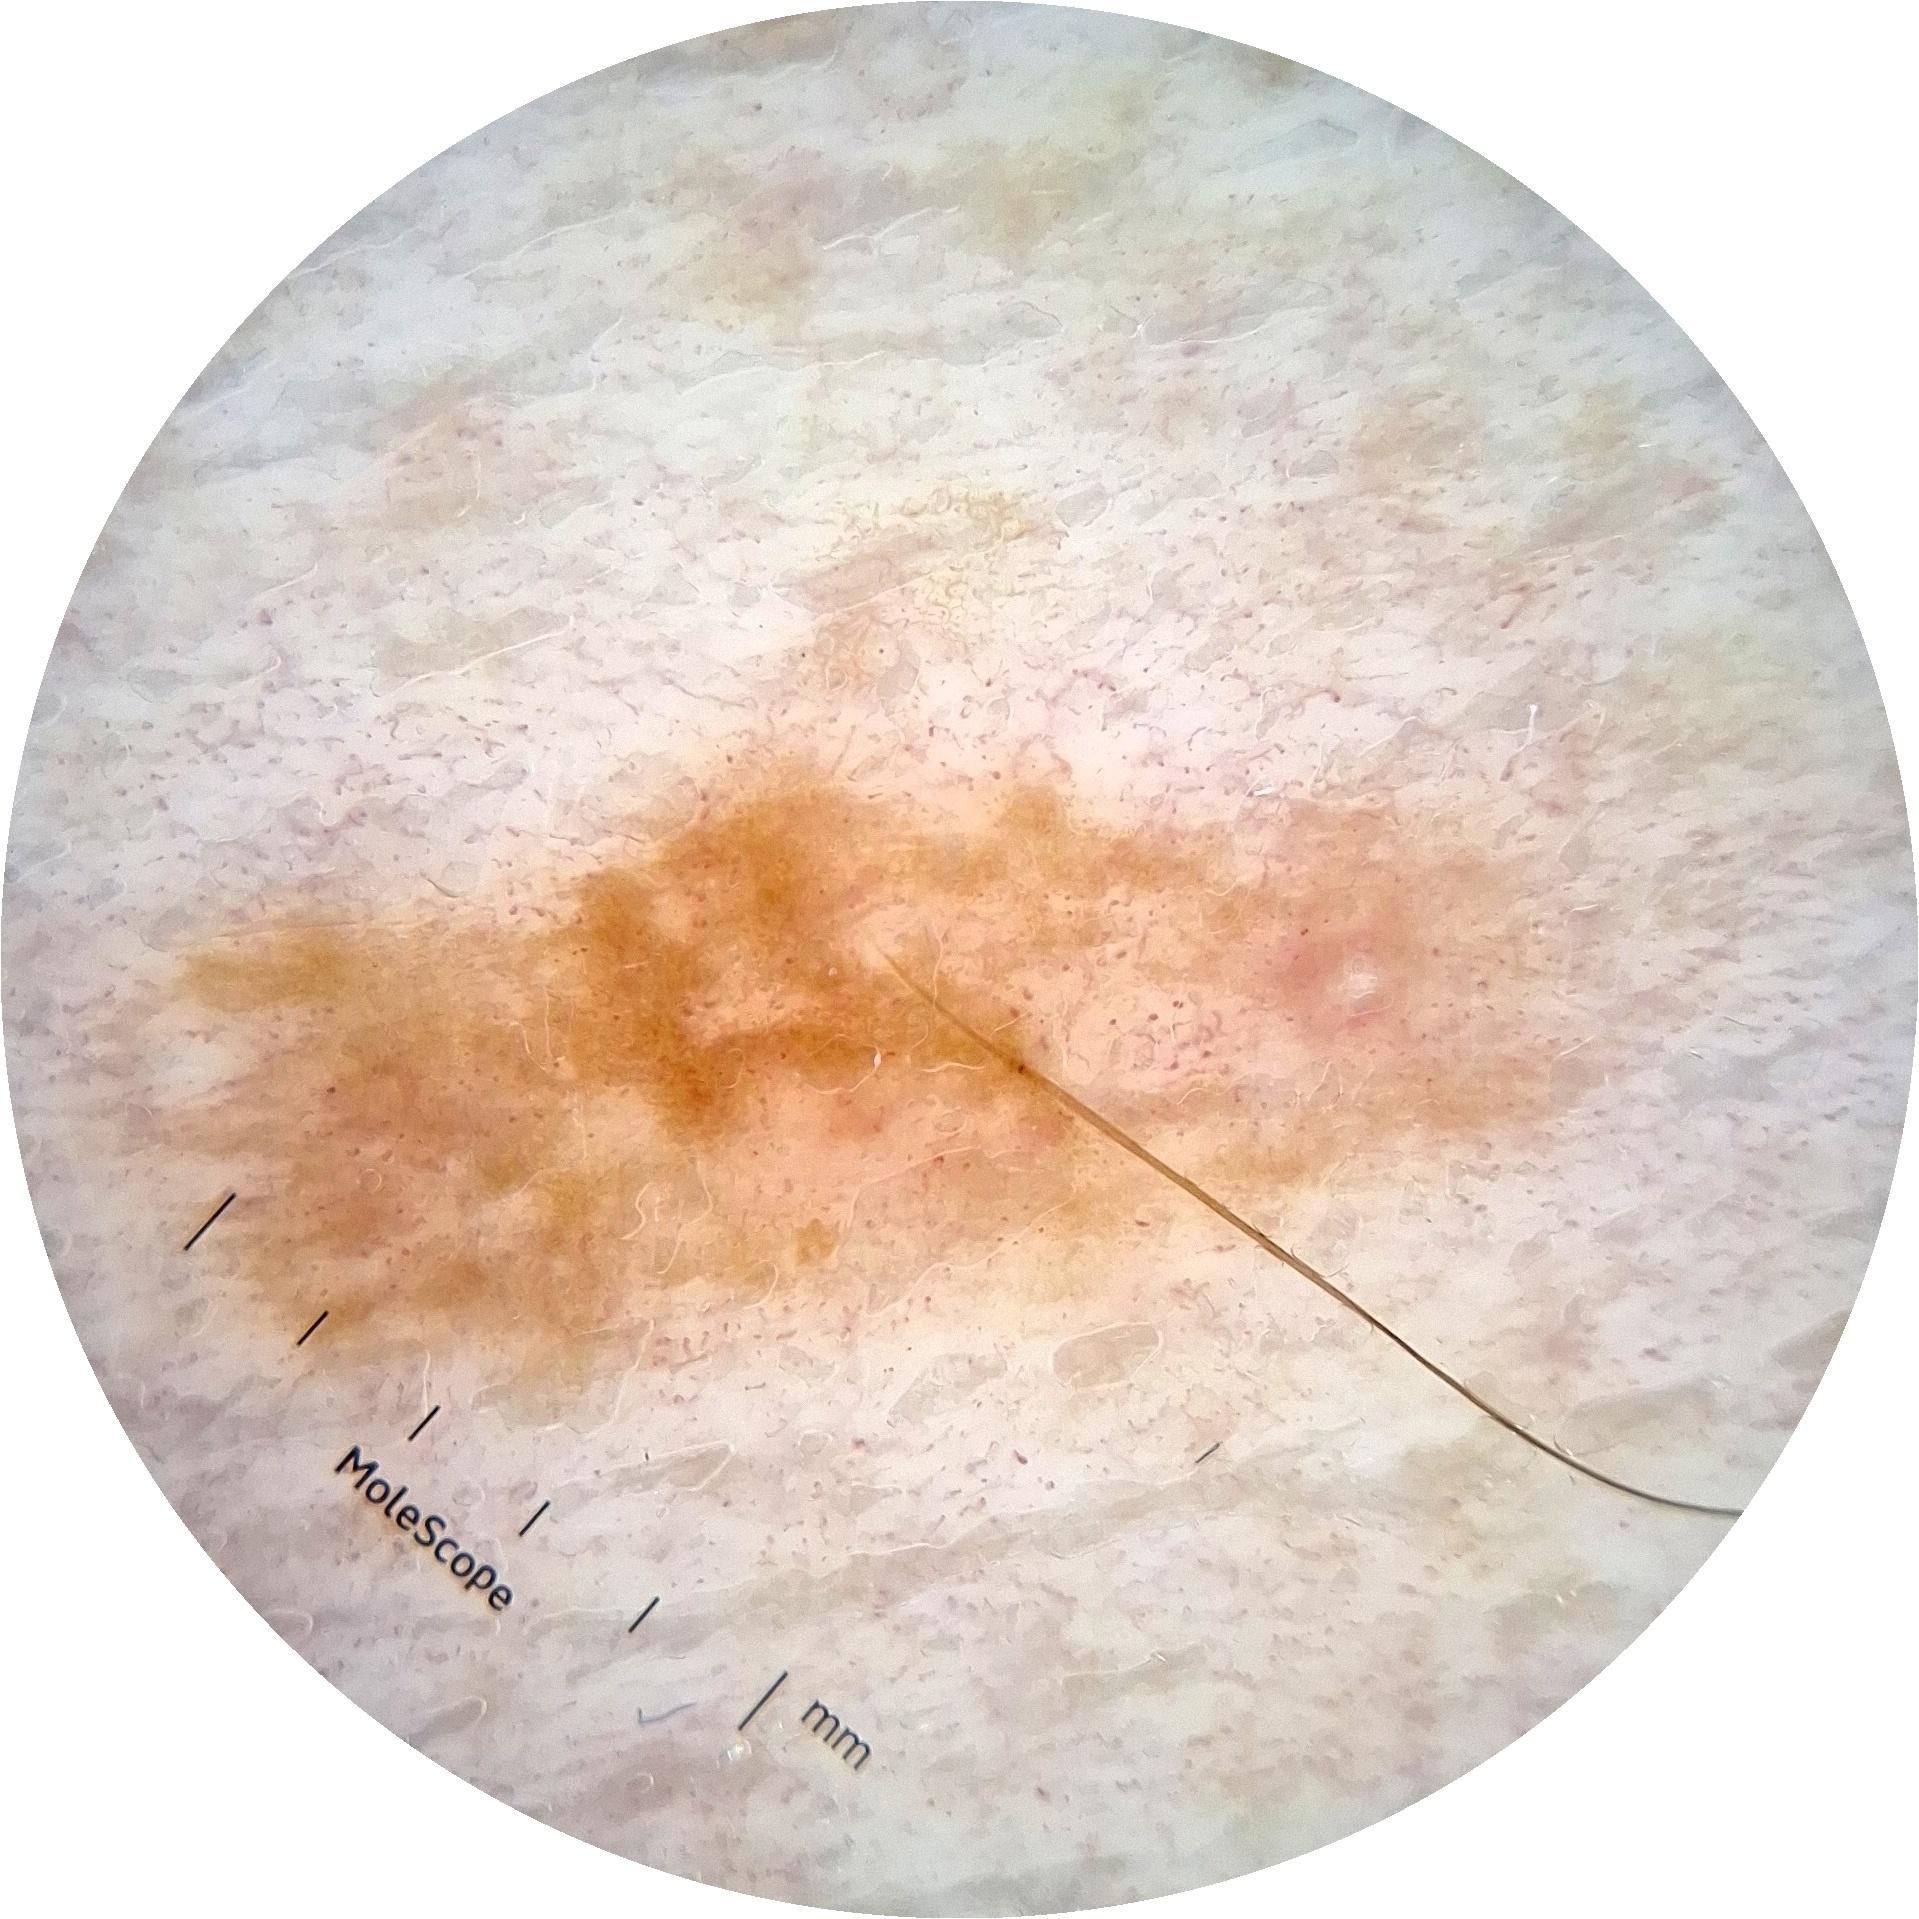

ISIC_6813604

873 x 873

acquisition_day 624

age_approx 75

anatom_site_1 Head and neck

anatom_site_general head/neck

diagnosis_1 Benign

diagnosis_confirm_type single image expert consensus

fitzpatrick_skin_type I

image_type dermoscopic